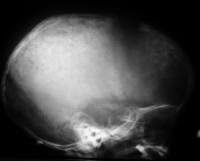

Gambar 6. Foto lateral tengkorak menunjukkan

pelebaran sutura koronal dan beberapa lusen di parietal dan tulang frontal

tengkorak dalam pasien dengan neuroblastoma metastatik.